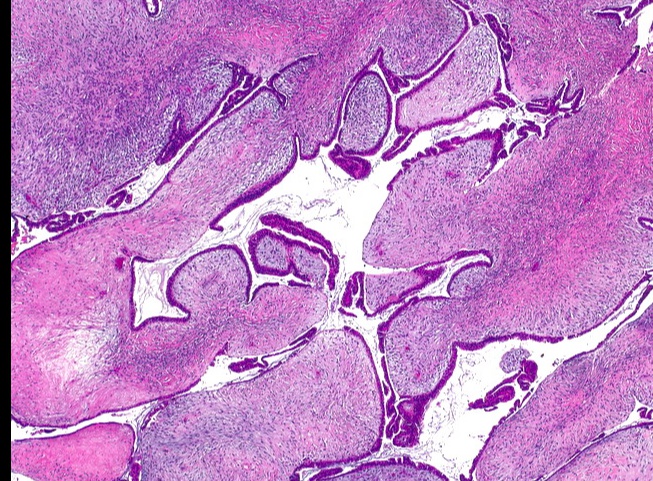

_On histology, characterized by a proliferation of intralobular stroma. Duct epithelium does not show signs of neoplasia, but may appear as a distorted by mass invasion.,

Fibroadenomas are small, firm, and mobile breast masses that occur due to proliferation of breast stroma and ducts, with stromal proliferation compressing the ducts to slits (black arrow) on microscopic examination.

sharply demarcated fibrosis and glands